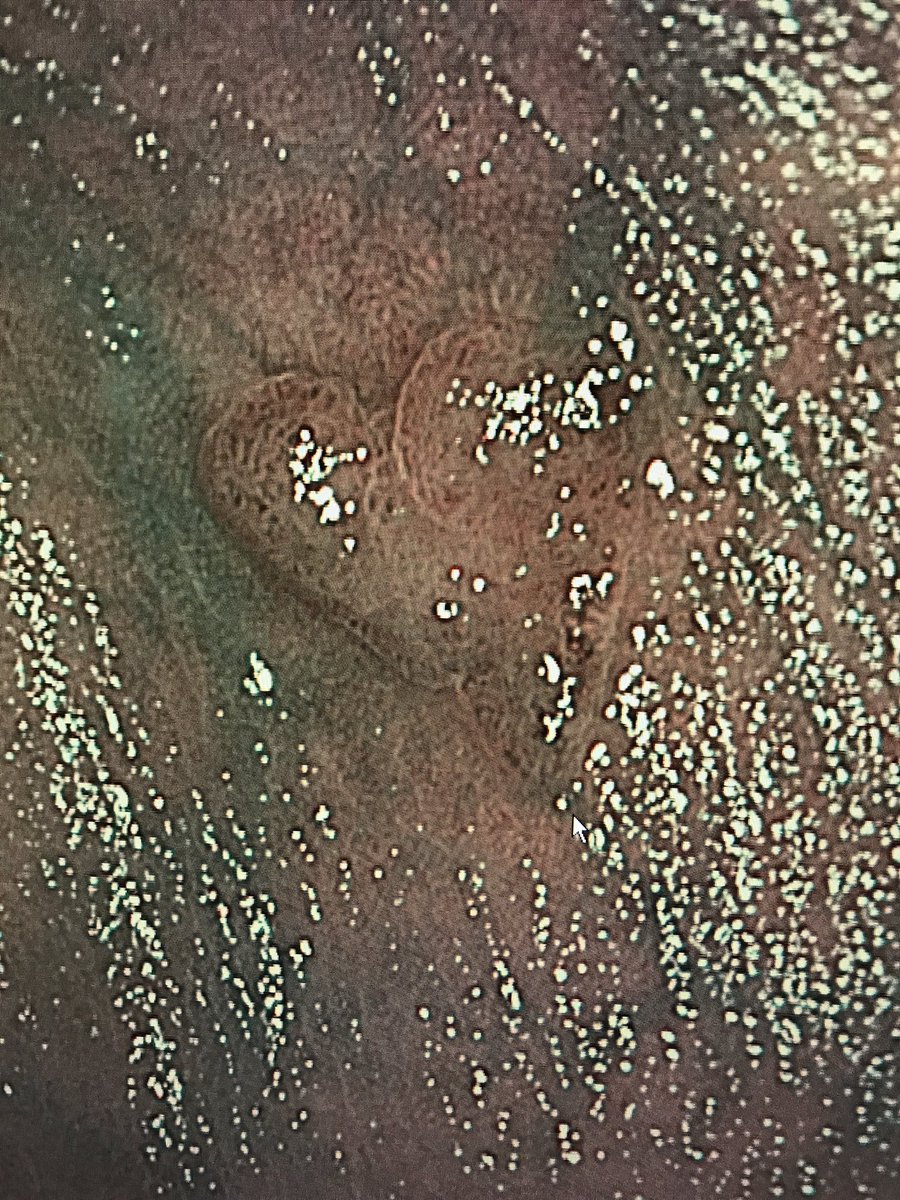

Ok - just one more polyp photo before the sun sets on #POLYPalooza Recognize this one? Hint: This polyp should have been found on Valentines Day. Remember: "Remove the Polyp, Prevent the Cancer" #CRCScreen19 #ColorectalCancerAwarenessMonth @AmCollegeGastro

MarkPochapin's tweet image. Ok - just one more polyp photo before the sun sets on #POLYPalooza Recognize this one?  Hint: This polyp should have been found on Valentines Day.

Remember:  "Remove the Polyp, Prevent the Cancer"

#CRCScreen19 #ColorectalCancerAwarenessMonth @AmCollegeGastro

This was my valentines find #Polypalooza

GI_Pearls's tweet image. This was my valentines find #Polypalooza